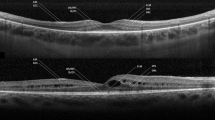

Extent of the preserved EZ line was also measured in horizontal and vertical scans, centered at the fovea (Fig. 2). All measurements were done using the calipers of the Heidelberg reader software [14].

Mean extent of the preserved EZ in the horizontal and vertical direction was 2856.4 μm (range = 518–8799 μm) and 2446.3 μm (range = 528–7914 μm), respectively, and strongly correlated to each other with r2 = 0.874, p < 0.001, but not to CDVA. None of these three measurements of the outer retina showed any significant correlation to preserved EZ extent.

The earliest histopathological change in the photoreceptors of eyes with RP is a shortening of the photoreceptor outer segments [18] while the loss of the cones is associated with reduced central vision at the end stage of the disease. Several OCT studies in RP patients study the correlation between the presence and continuity of the inner segment/outer segment (IS/OS) line, what is now called as EZ and the visual function [13, 17,18,19,20,21,22,23,24]. Using Fourier Domain OCT in eyes with retinal dystrophy, Lim et al. have demonstrated a 11% decrease in the macular inner retina layer and a 45% decrease in the macular ORL compared with normal [25]. Sandberg et al. [21] found a significant correlation between the grade of EZ and the visual acuity in RP patients. Aizawa et al. also reported that the length of the EZ significantly correlates with the retinal sensitivity and visual acuity of RP patients [24, 26]. The positive correlation between central visual acuity and extent of preserved EZ line possibly indicates that the degeneration of the central cones correlates with peripheral rods’ degeneration. In our study, we have found no significant correlation between CDVA, which signifies the cone function, and the extent of preserved EZ on SD-OCT. This could be attributed to early or late onset of cone degeneration secondary to the genetic heterogeneity of RP. Thus, the preserved EZ, rather than central visual acuity, may correlate better with visual field loss and retinal sensitivity on microperimetry.